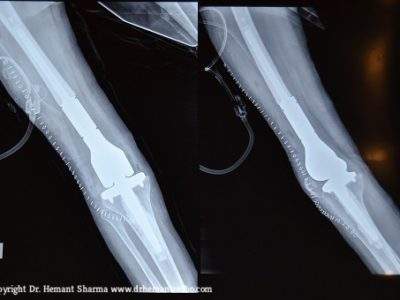

IMPLANT

POST-OPERATIVE